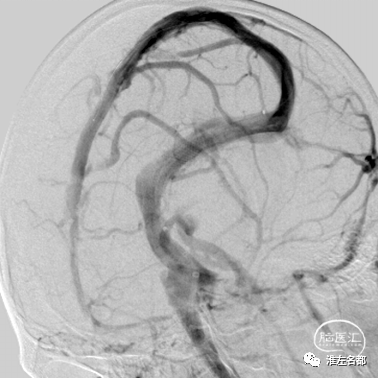

此脑静脉窦血栓患者合并硬脑膜动脉瘘,

经右侧颈动脉造影,

动脉期右侧横窦-乙状窦提早显影。